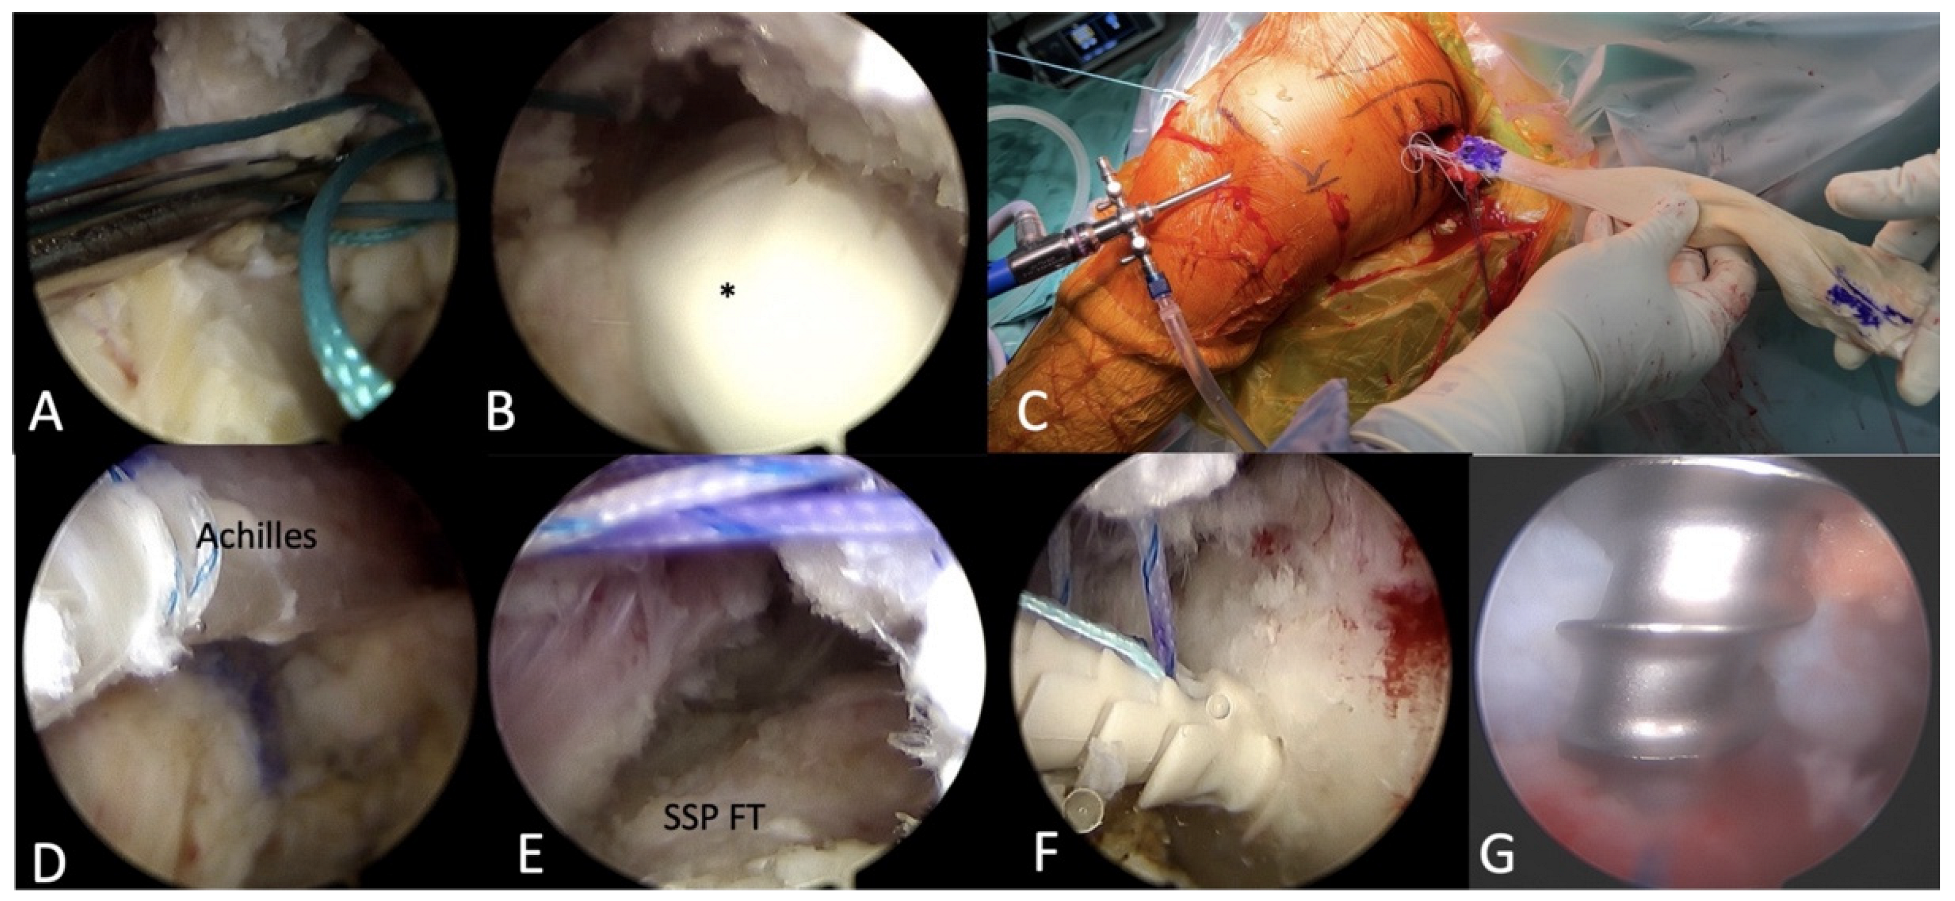

2.2.3. Arthroscopic Achilles Allograft Tendon Passage and Fixation

2.2.4. Merging the Achilles Allograft with LTT